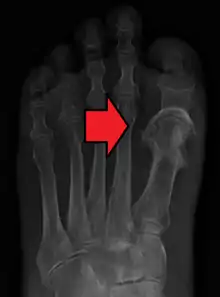

Orthopaedic injuries especially fractures of the long bones are the most common cause of fat embolism syndrome (FES). The rates of fat embolism in long bone fractures vary from 1% to 30%. The mortality rate of fat-embolism syndrome is approximately 10–20%.[7] However, fat globules have been detected in 67% of those with orthopaedic trauma and can reach as high as 95% if the blood is sampled near the fracture site. As the early operative fixation of long bone fractures became a common practice, the incidence of FES has been reduced to between 0.9% and 11%.[6]